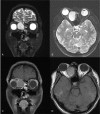

Patient concerns: We report a case of a 37-year-old man who presented with painless proptosis of the right eye and diplopia.

Diagnoses: The preoperative finding was mucocele of the ethmoid sinus.

Interventions: We performed endoscopic sinus surgery, which included uncapping of the anterior and superior wall of the mucocele.

Outcomes: The mucocele was treated safely and effectively without touching the medial orbital wall.